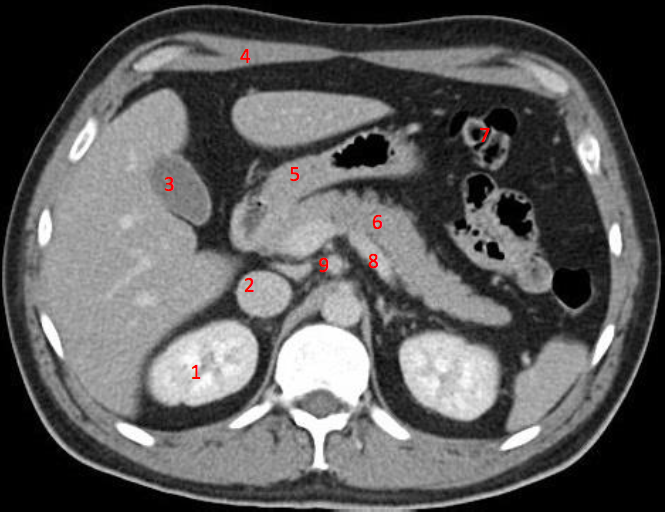

Number 8?

Descending colon

Number 7?

Bowel (probably large)

Number 2?

IVC

Number 4?

Rt lobe liver

Rt lobe of liver

Number 6?

Stomach